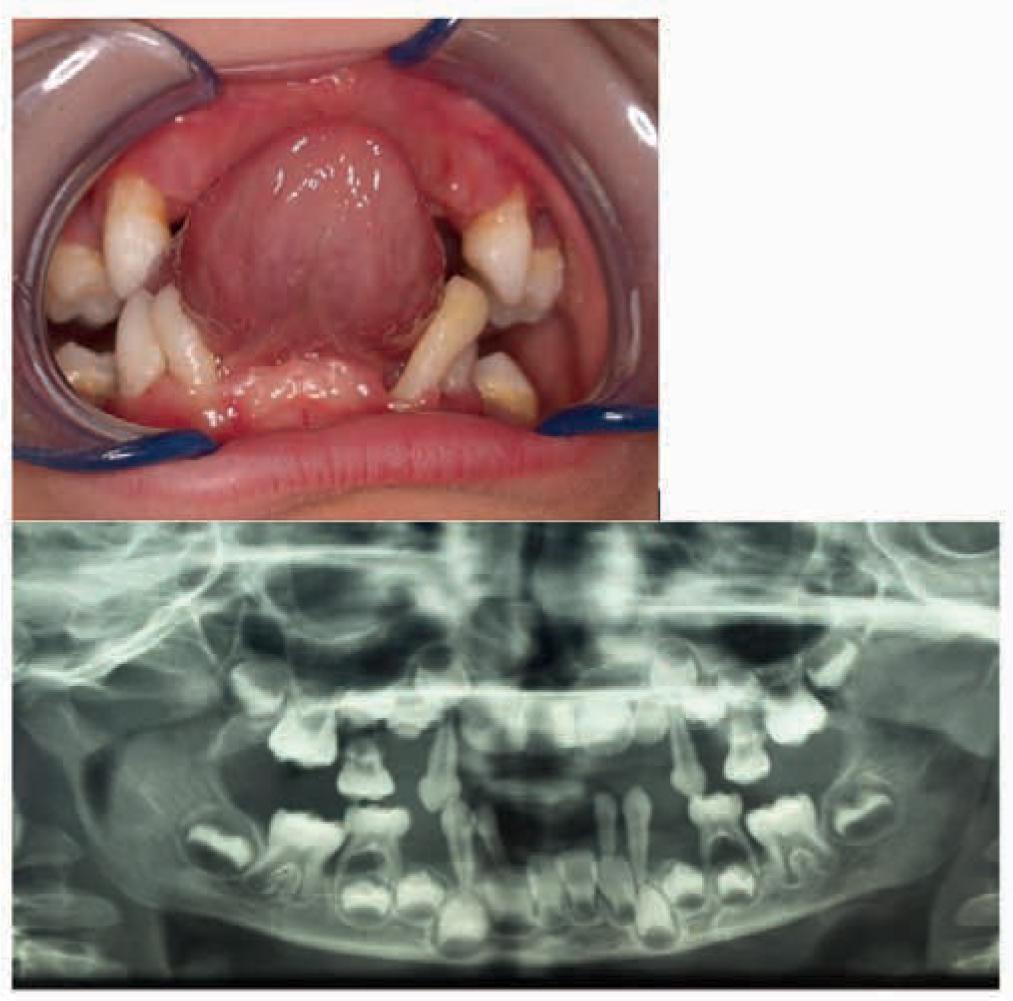

Medical records of 43 out of 44 patients with Langerhans cell histiocytosis were included in the study. One patient was excluded from the study due to the lack of dental examination as part of the diagnostic process. Age at diagnosis ranged between 0.33 and 16.33 years (mean 5.95 ± 4.66 years). Study group characteristics, including age at LCH diagnosis, sex, clinical form of LCH, as well as organs and systems involved, is presented in the form of a table (Tab. 1). Of 34 cases of single-system LCH, 31 (91.2%) involved bones, and 3 involved the skin (7.8%). Multisystem LCH most often involved the skin (8/9), followed by the bones (7/9) and lungs (5/9). Bone manifestations usually occurred in the craniofacial region (n = 23), including the skull (n = 11), mandible/maxilla (n = 7), orbit (n = 6), and zygomatic bone (n = 1). Less common locations included the spine (n = 8), long bones (n = 7), pelvis (n = 2), clavicle (n = 2) and ribs (n = 1). Diabetes insipidus (DI) was reported for four patients. Oral lesions in the form of gingivitis, pathological tooth mobility or expansion of the alveolar mandibular bone were observed in seven patients (Table 2, Figures 1–3). One patient was diagnosed with LCH based on histopathology of a gingival biopsy specimen.

A 4-year-old patient. Premature loss of incisors and first maxillary and mandibular molars, generalised decrease in the translucency of the alveolar maxillary and mandibular bone with pronounced bone atrophy in the region of right mandibular cuspid and second mandibular molars, as well as root resorption of second mandibular molars